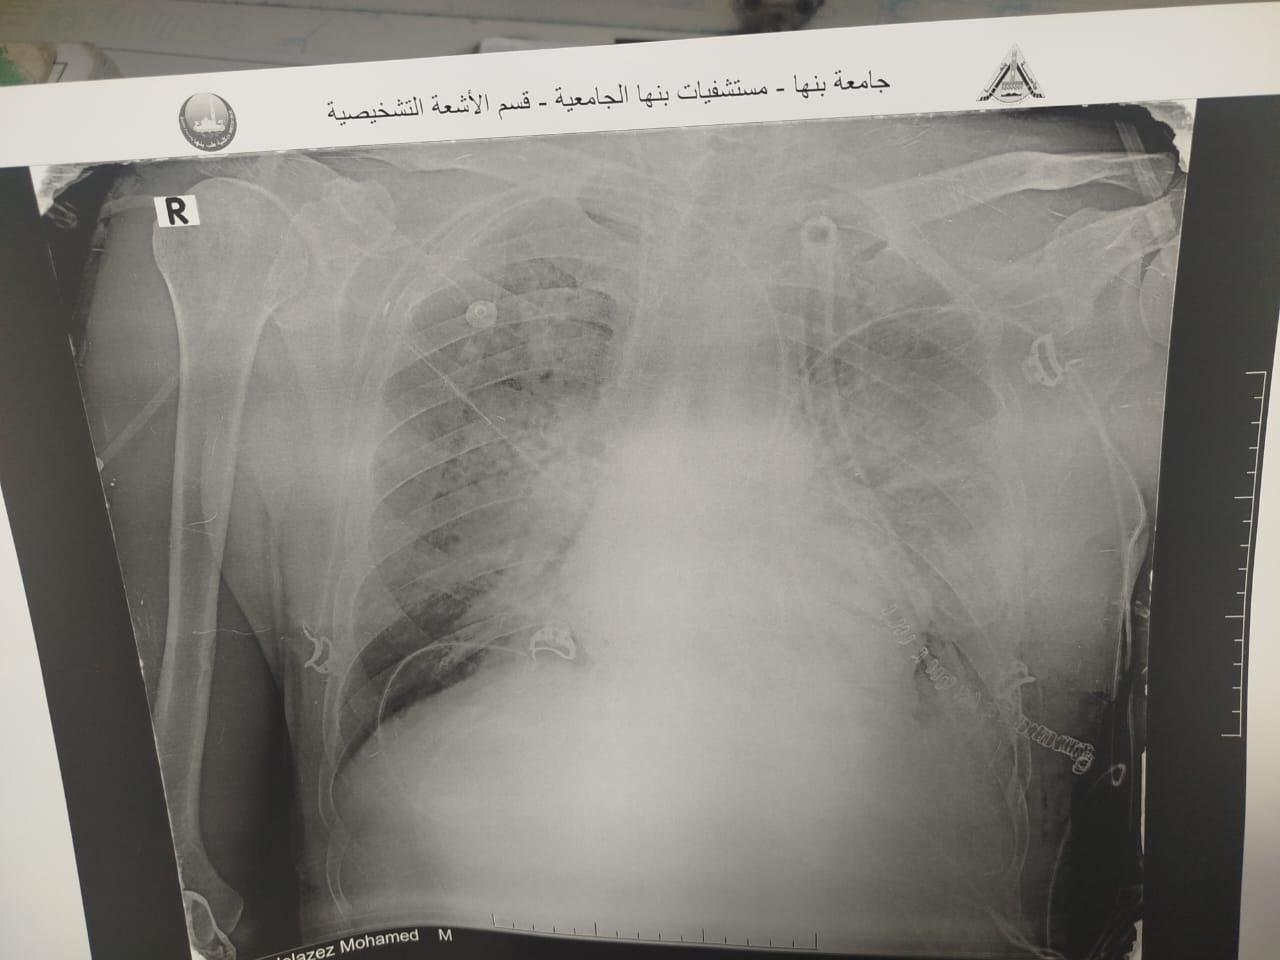

الأشعة الخاصة بالمريض